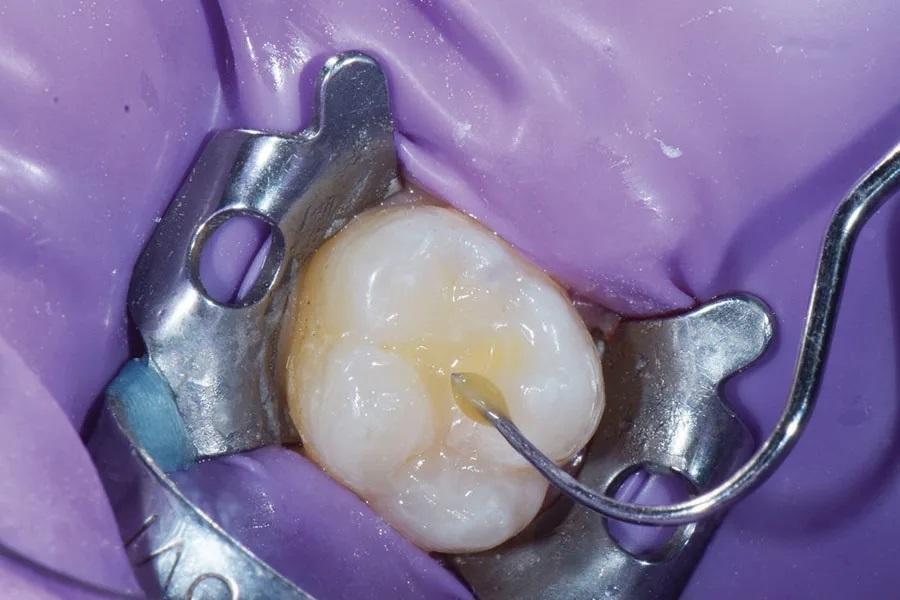

На окклюзионную поверхность уложена тонкая полоска тефлоновой ленты, чтобы предотвратить прилипание используемого далее «штампа» к композиту (Фото 10). «Штамп» сориентирован относительно зуба и плотно прижат для вдавливания дооперационной окклюзионной топографии в поверхность композита (Фото 11 и Фото 12). Излишки композита легко удалены моделировочным инструментом (OptraSculpt, Ivoclar) (Фото 13). До финальной полимеризации нанесен тинт (Creative Color Honey Yellow, Cosmedent) для эстетической репродукции фиссур (Фото 14), после чего произведена засветка 20 секунд. Окончательная реставрация финишно обработана и отполирована (A.S.A.P. Polishers, Clinician’s Choice).

Фото 11. «Штамп» правильно сориентирован и прижат для переноса дооперационной окклюзионной топографии на композит.

Фото 12. Вид зуба после снятия «штампа».